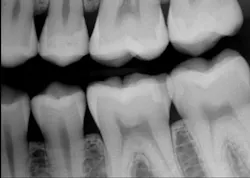

Figure 1: Apparently small caries on distal of mandibular second premolar

Figure 2: Tooth isolated and ready for tooth preparation with No. 329 bur on mandibular second premolar

Figure 3: Tooth preparation initially cut (left) and cut deeper (right) showing inadequacy of current generation of digital bitewings to show full extent of caries as related to radiograph